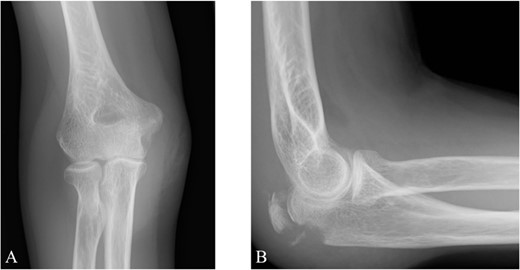

A 65-year-old healthy Japanese woman fell on her hands with her right elbow extended. She presented to our hospital with pain and swelling in the right elbow joint; active extension was impossible. X-rays showed a triceps tendon avulsion fracture (Fig. 1). Her bone mineral density, using dual X-ray absorptiometry, was 71% of the young adult mean for the lumbar spine. She was diagnosed with an avulsion fracture of the right olecranon (AO classification: 2U1A1) and underwent surgery 7 days post-injury.

Plain radiographs of the right elbow show no abnormal findings in the anteroposterior view (A); however, an avulsion fracture of the olecranon is observed in the lateral view (B).